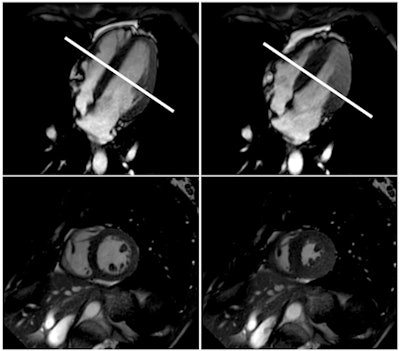

Cardiac MRI shows normal left-ventricular function in the standard horizontal long axis (upper two images) and corresponding short axis (lower two images) in diastole (left) and systole (right) at the midventricular section of the heart (white line). Images courtesy of RSNA and Dr. Jonas Dörner.The MRI exams allowed the researchers to observe the cardiovascular changes involved in the diving reflex in real-time. During apnea, the amount of blood flowing to the brain through the carotid arteries increased and then leveled off.